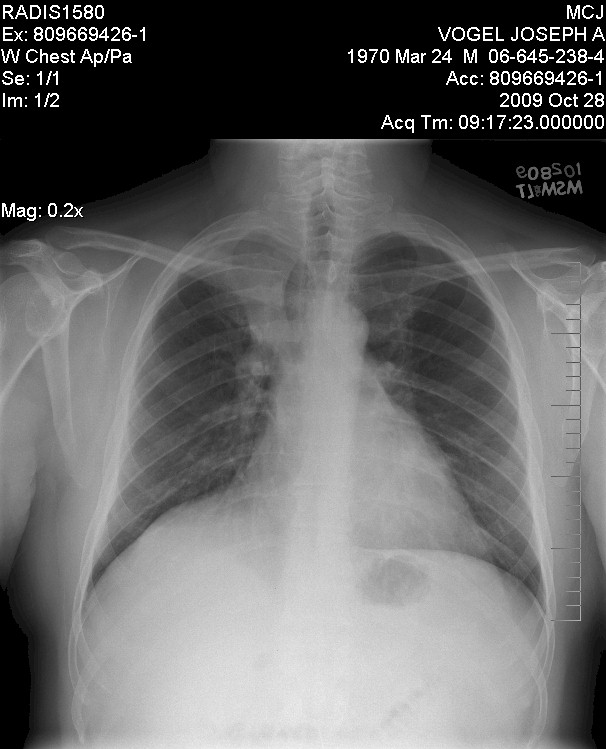

X-Ray of my chest done by Mayo and indicated as

"abnormal lung" in October 2009:

So, as you can see, basically the EXACT same!

Which in one way was good since it had not gotten worse, BUT it was the exact

same so Solantic totally missed it!

Arg!